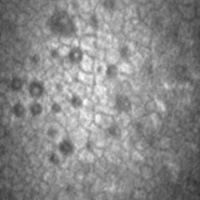

Dry AMD

- Apeliis, a phase 3, multicenter, randomized, double-masked, sham-controlled study to compare the efficacy and safety of intravitreal APL-2 therapy with sham injections in patients with geographic atrophy (GA) secondary to age-related macular degeneration (AMD). Primary Objective is to evaluate the efficacy of APL-2 compared to sham injection in patients with GA secondary to AMD assessed by change in the total area of GA lesions from baseline as measured by fundus autofluorescence (FAF).

- GEMINI-001, a Genetic Screening Study to Evaluate Long-term Clinical Outcomes in Subjects with Non-Central Geographic Atrophy (GA) Who Are Carriers of High-Risk Genetic Complement Variants Associated with Dry Age-related Macular Degeneration(AMD) GEM-NH-001-Cohort 0 is a prospective, multicenter, longitudinal registry, consisting of 375 participants with non-central geographic atrophy (GA) secondary to dry age related macular degeneration (AMD), who are carriers of known genetic variants associated with AMD. The primary objective of the GEM-NH-001 study is to develop a participant dry AMD registry which can allow for collection of substantial longitudinal data to further increase understanding of disease progression and to support future interventional studies.